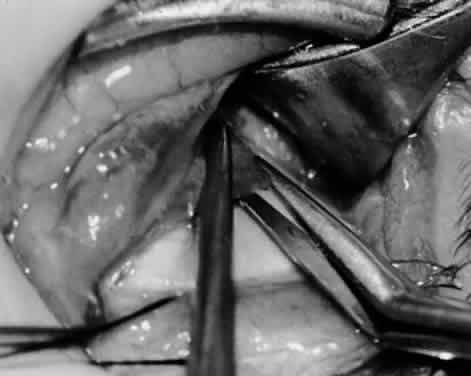

Fig. 28. The inferior oblique muscle is drawn further into the operative field, and a 3-0 Vicryl suture ligature is applied about the belly of the muscle.

Fig. 29. Cautery is used to sever the inferior oblique muscle and to provide hemostasis.

Fig. 30. The stump of muscle is placed through the Tenon's capsule opening. The surgeon must apply sufficient cautery to prevent postoperative bleeding.

Fig. 31. The inferior oblique muscle stump is visible at the opening in the Tenon's capsule before closure with 6-0 or 7-0 Vicryl suture. The S-28 half-circle curved needle is preferred to the S-29 needle, which has a 3–8-circle curve.

Fig. 32. The Tenon's capsule opening is closed with 6-0 or 7-0 Vicryl suture to place the inferior oblique muscle entirely outside Tenon's capsule.